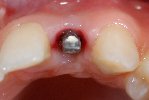

- Komplette Regeneration der Pappille 3 Monate nach der Eingliederung der Implantatkrone

- Vollkeramische Restauration auf Implantat